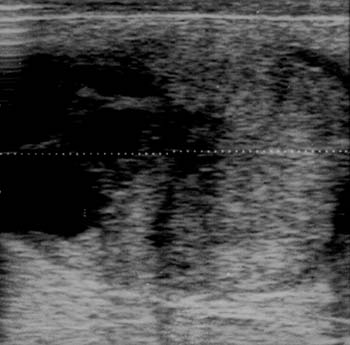

Transrectal palpation and ultrasound: The left ovary was small (3 cm), firm, and had no follicles. The right ovary was enlarged and firm with several soft areas. Ultrasound revealed that the right ovary measured 10 x 7 cm and was composed of homogenous echogenic tissue and several cystic structures. No other abnormalities were observed.

Ultrasound image of right ovary: